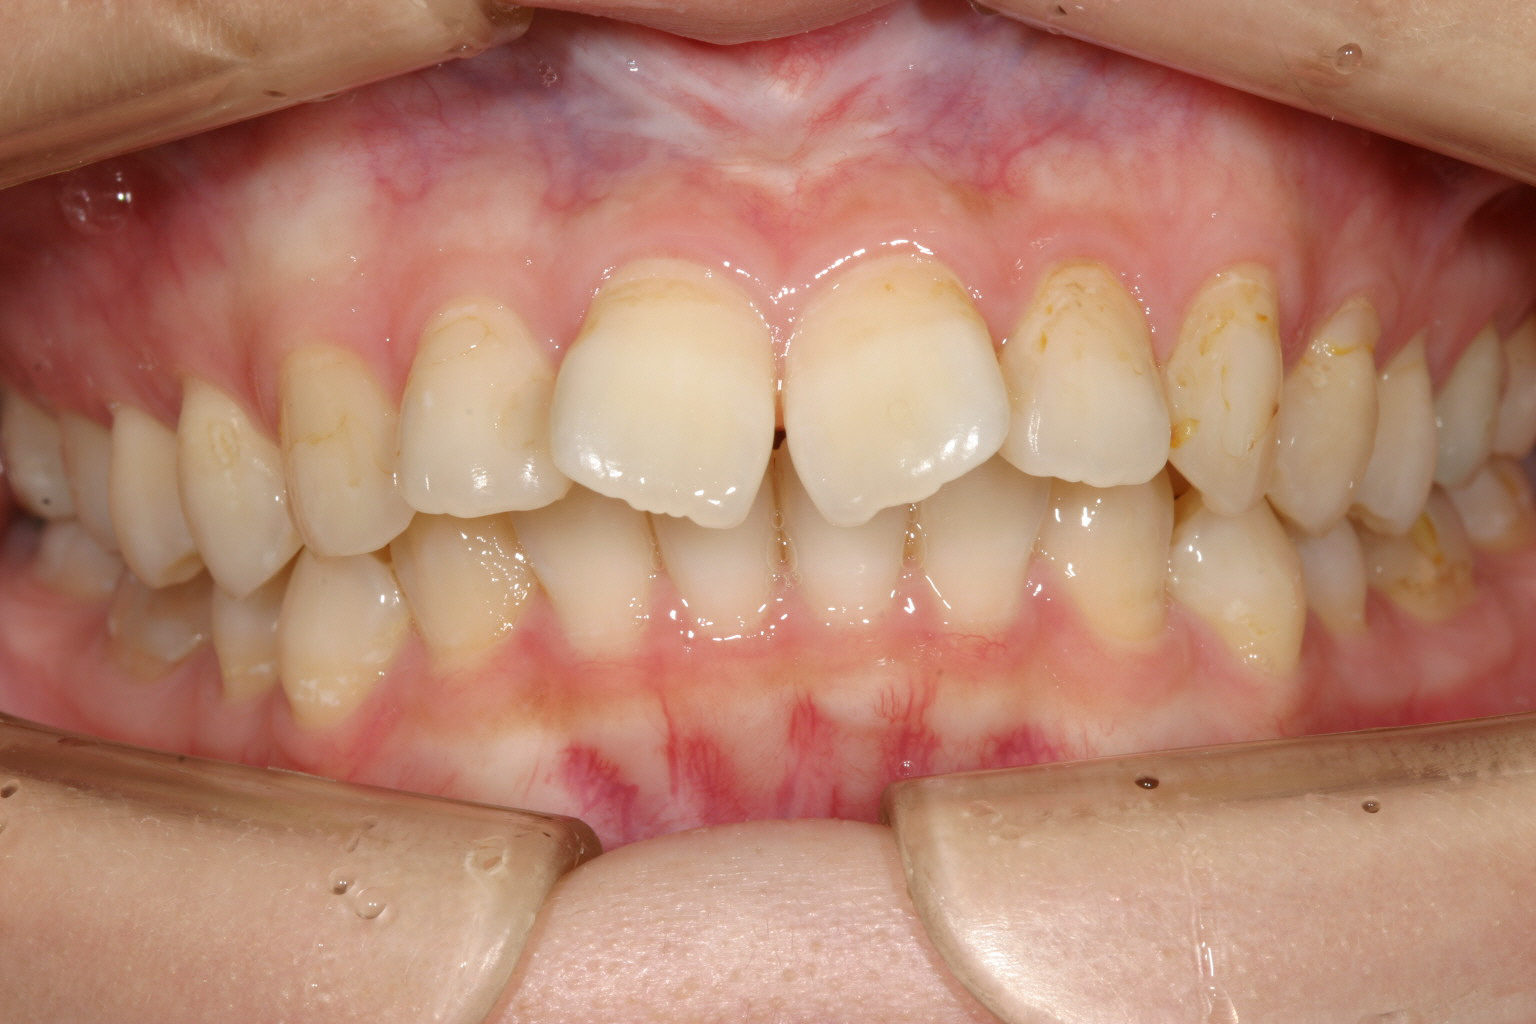

前歯かなり捻転してますね~

凄いでっぱです。 特に歯が捻転してますから余計に出っ歯感が増します。